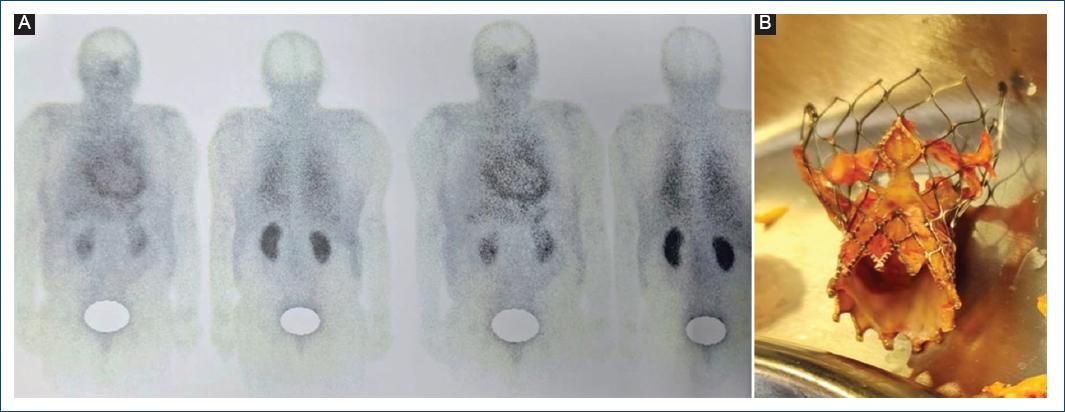

Figure 2 A: technetium-99m-ubiquicidin 29-41 SPECT-CT scan: focal uptake in the prosthetic aortic valve area and pericardium. B: transcatheter aortic valve replacement endoprosthesis extracted with fibrin and signs of edema on the prosthetic leaflets and skirt. SPECT-CT: single photon emission computed tomography-computed tomography.